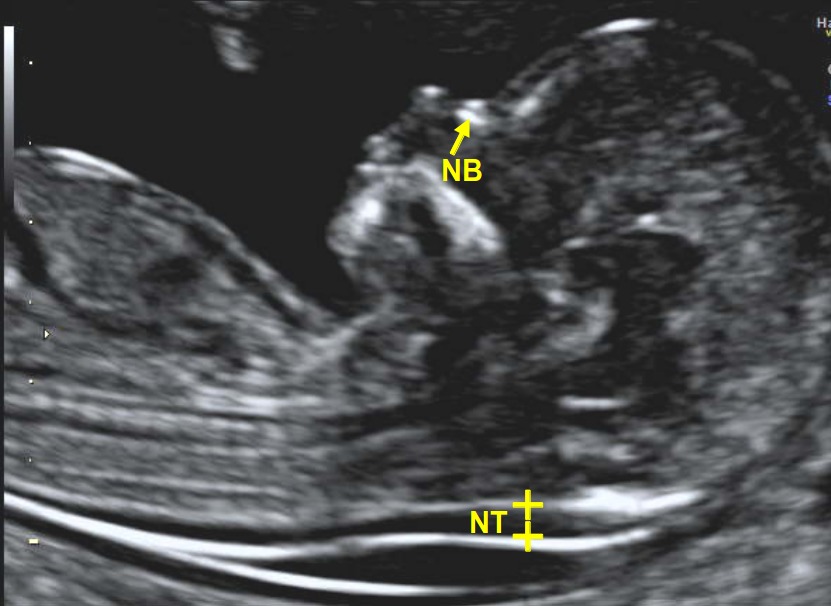

Wat Is Een Nekplooi. Zoals eerder aangehaald is de nekplooi een translucent gebied te zien op echografie die normaal verdwijnt na 14 weken zwangerschap. Toch willen wij het zeker weten. Wat is de nekplooi. Bij een zwangerschapsduur tussen 11 en 14 weken is bij elke foetus een klein schilletje vocht onder de huid in de nek aanwezig.

De specialist in het radboud ziekenhuis zei dat het echt heel normaal is dat de nekplooi vóór 11 weken en 3 dagen nog dikker kan zijn omdat de lymfe zich dan ontwikkelen. Mischien heeft de specialiste een ander reden voor verder onderzoek denk dat je dat best eens kan vragen. In het nekje is dan vaak een beetje vocht aanwezig deze vochtophoping is gewoonlijk niet meer dan 3 mm dik. Zoals eerder aangehaald is de nekplooi een translucent gebied te zien op echografie die normaal verdwijnt na 14 weken zwangerschap. De breedte van dit schilletje wordt gemeten tot op 01 mm nauwkeurig. De nekplooi is een dun vochtlaagje onder de huid in de nek.